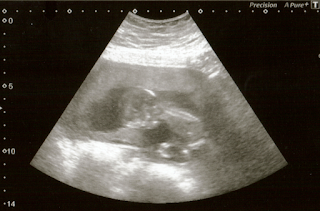

A few weeks have gone by since the last update and it's time to write another update on how me and Larva are doing. We had a growth ultrasound scan on the 21st of January and got some new pictures of Larva then. Unfortunately things went as I suspected and the technician was unable to do the nuchal translucency (aka NT) measurement, so we had to wait until February 1st (last Monday) to have blood drawn for the quadruple test. The results for it came on Friday with likelihoods of less than 1 to 10000 that there's anything massively wrong, and so we were able to give a go-ahead for those members of the family who already knew, that they can tell others that we're having a baby!

The due date was now shifted a week earlier than what the previous scan said, so now it's the 23rd of July. Scan and blood test results have been relieving for not only knowing that Larva is doing all right, but also finally being able to go public and as a result being able to ask other recent mummies for advice on what to buy, what to do and what to avoid. I can now *finally* shop for some maternity kit and can really start planning for other purchases. The only purchases I've done so far for specifically pregnant me has been two pairs of non-wired full support bras and an exercise ball, which I plan to keep and use as an office chair after Larva's made The Exit. The only big 'purchase' we've done right after the quadruple test results came in was to book in NCT antenatal classes in May and June.